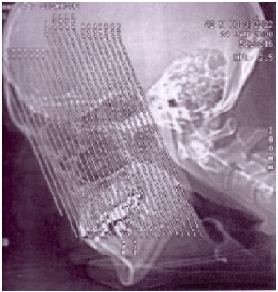

Com relação ao estudo tomográfico das cavidades paranasais, observe as imagens:

Baseado no topograma (

scout

) demonstrado acima, pode-se afirmar que os cortes serão obtidos no plano

A

axial.

B

sagital.

C

coronal.

D

parassagital.